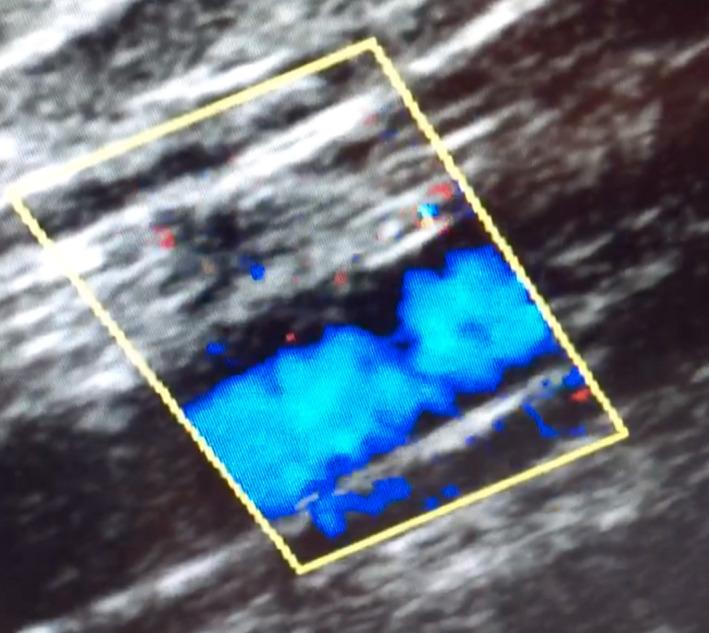

使用FlowTriever系统对Impella相关的髂动脉血栓进行经皮血栓切除术。

Percutaneous thrombectomy of Impella-associated iliac artery thrombosis using the FlowTriever system.

Percutaneous thrombectomy using the FlowTriever system is a potentially safe and effective alternative to surgery in cases of Impella-associated peripheral arterial thrombosis.

在Impella相关的外周动脉血栓形成病例中,使用FlowTriever系统进行经皮血栓切除术是一种潜在安全有效的手术替代方案。